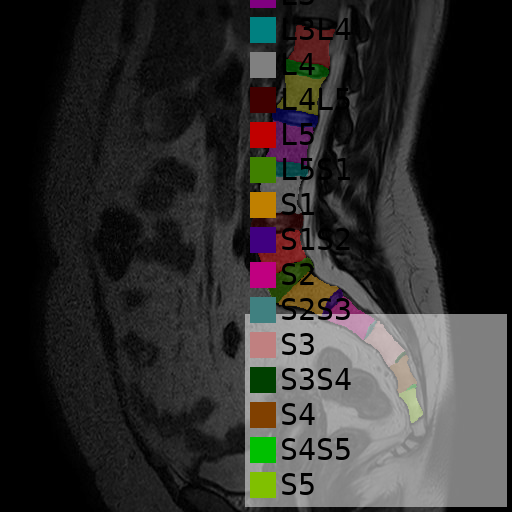

I developed MRI-SEG, a cross-platform software package for automatic classification and segmentation of Spine MRI images. The tool features a custom GUI designed for ease of use on both Windows and Linux systems. MRI-SEG integrates a deep learning model that I personally built and trained, enabling accurate segmentation and diagnosis support for spinal structures in MRI scans.

Overview of the performance of a customized nnU-Net version (used in the initial training step).